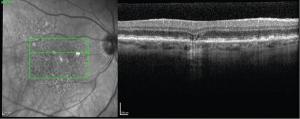

In an attempt to halt the progression of dry AMD and geographic atrophy, the use of high-resolution optical coherence tomography becomes pivotal.